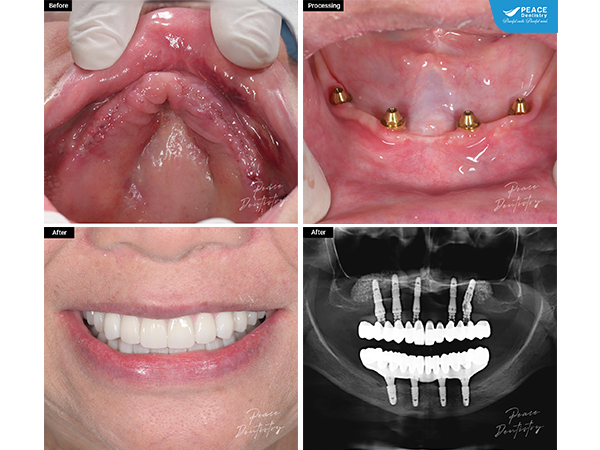

cấy ghép implant All-On-5 hàm trên & All-On-4 hàm dưới cho nữ khách hàng lớn tuổi đã mất hết răng

(Ca cấy ghép implant All-On-5 hàm trên & All-On-4 hàm dưới cho nữ khách hàng lớn tuổi đã mất hết răng. Thay thế hàm tháo lắp ban đầu, giúp khôi phục chức năng ăn nhai tốt). Xem chi tiết ca lâm sàng tại đây (**)